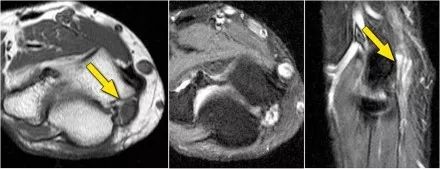

下面是MR● 冠状图片:侧副韧带完全剥离(黄色箭头)。桡骨头是半脱位的。由于骨折引起的冠突骨髓水肿(红色箭头)。● 矢状面观:桡骨头稍后有点半脱位(黄色箭头)。大量积液和囊后破裂。● 由于冠状突的撞击(红色箭头)导致的头颅后侧的挫伤。所有这些迹象都是后脱位的结果。